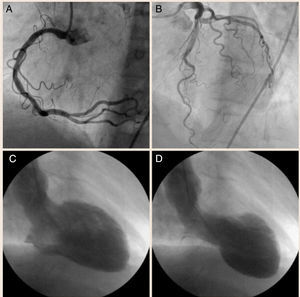

A) Coronariografía demostrando coronaria derecha sana, sin lesiones. B) Coronariografía evidenciando tronco principal izquierdo, arteria coronaria descendente anterior y arteria circunfleja sin lesiones obstructivas. C) Ventriculografía en diástole. D) Ventriculografía en sístole mostrando acinesia en los segmentos inferolateral basal y apical.

La troponina I resultó elevada (2.86ng/ml) y dadas las características del dolor se sugirió la posibilidad de un síndrome aórtico agudo, motivo por el cual se realizó una angiotomografía computarizada toracoabdominal cuyo resultado fue normal. Con la impresión diagnóstica de un infarto agudo de miocardio (IAM), la paciente fue llevada a coronariografía, donde se observaron coronarias sanas, sin lesiones ateromatosas obstructivas (figs. 2A y B). La ventriculografía demostró acinesia en los segmentos inferolateral basal y apical (figs. 2C y D), con una fracción de eyección del ventrículo izquierdo (FEVI%) estimada en el 35%. Una ecocardiografía realizada al ingreso confirmó los hallazgos de la ventriculografía y no reveló enfermedad valvular asociada.